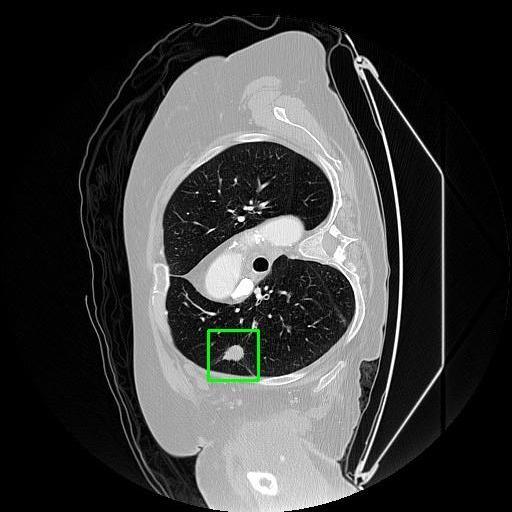

We developed an AI-based system using deep learning models for analyzing lung CT scans to detect and classify pulmonary nodules. We chose the YOLOv11 architecture for its enhanced object detection capability and adapted it specifically for medical imaging, incorporating pixel-level precision and severity classification.

Classification into three severity levels with colored bounding boxes.

Designed a severity classification system that categorizes nodules into null, moderate, and severe using colored bounding boxes, assisting in rapid clinical decision-making.